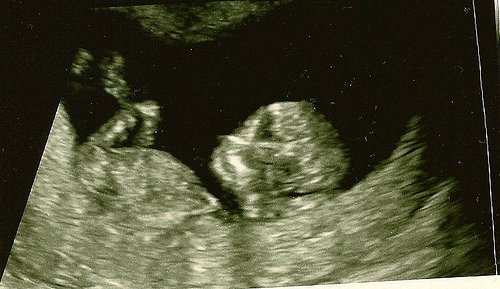

каквото Бог даде,важното е да са здравички.

каквото Бог даде,важното е да са здравички.

А това в коя седмица се случва ?Кога се оформя ?

А това в коя седмица се случва ?Кога се оформя ?